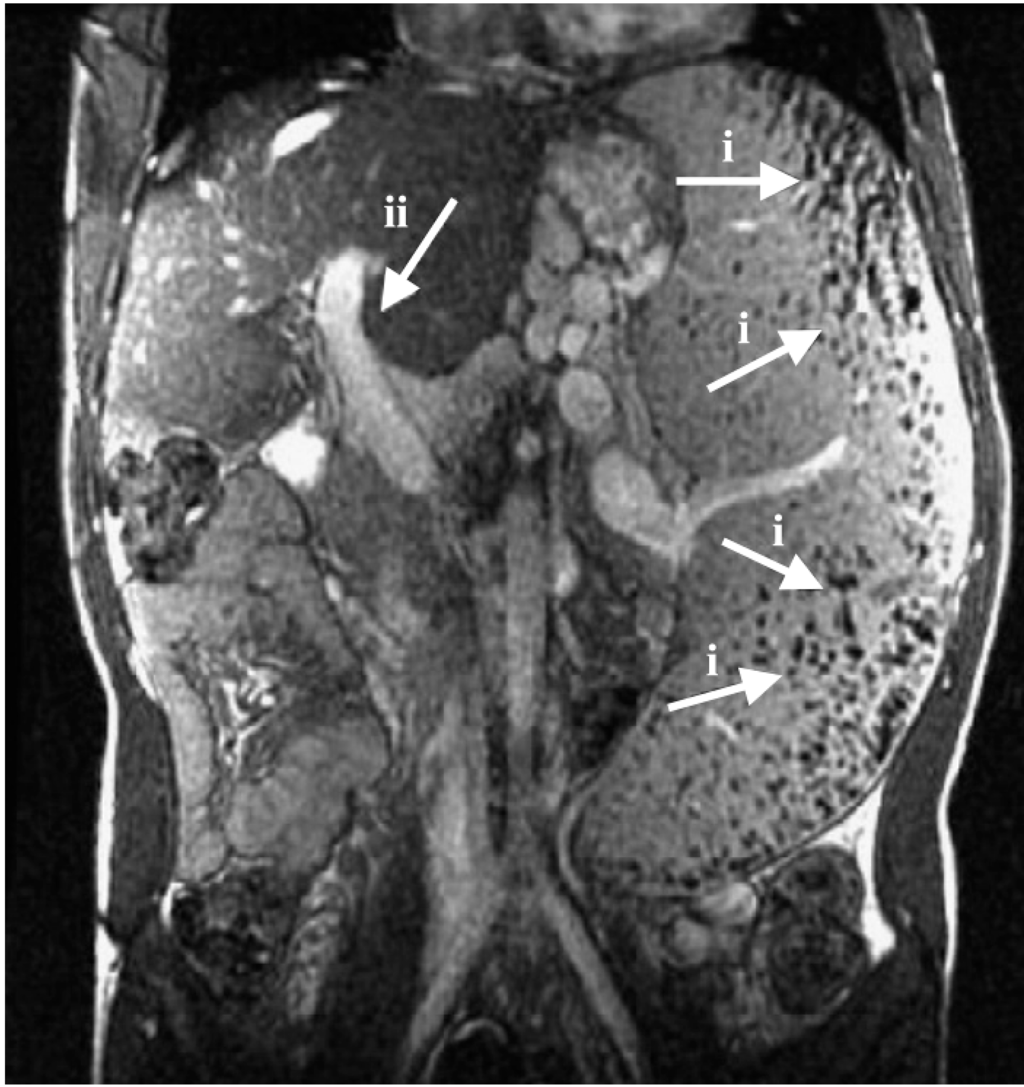

Schistosomiasis is a type of parasitic infectious disease affecting at least 230 million individuals per year in developing countries. It is caused by the trematode parasite worms, of the genus schistosoma. The disease is classified into two major types; (a) intestinal schistosomiasis caused by S. guineensis, S. mekongi, S. mansoni, S. japonicum, and S. intercalatum, and (b) urogenital schistosomiasis caused by S. haematobium. Rapid multiplication and transmission of the schistosoma parasites lead to more infected people each year. Furthermore, there is a high mortality rate of this disease, above 200,000 deaths per year in sub-Saharan Africa [5]. Shistosomiasis infection happens when parasites in larval forms produced by snails in fresh water, penetrate the skin, often of the feet, that is exposed to infested water. The larva then turns into mature schistosomes in the body. The adult female worms can produce eggs in the blood vessels causing immune reactions and damaging tissues while others get out of the body through urine or faeces.